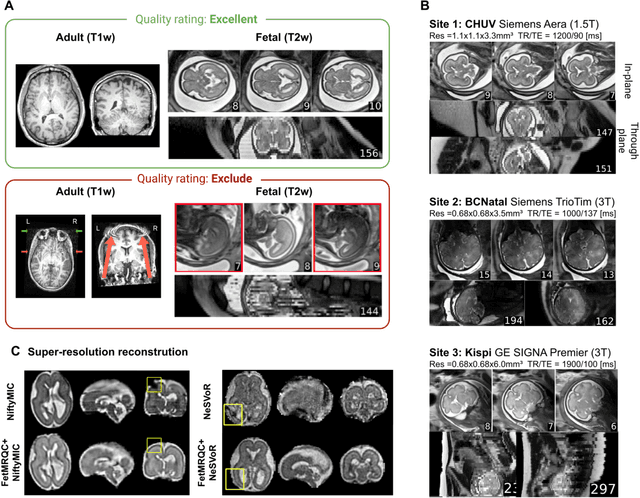

Abstract:Quality control (QC) has long been considered essential to guarantee the reliability of neuroimaging studies. It is particularly important for fetal brain MRI, where acquisitions and image processing techniques are less standardized than in adult imaging. In this work, we focus on automated quality control of super-resolution reconstruction (SRR) volumes of fetal brain MRI, an important processing step where multiple stacks of thick 2D slices are registered together and combined to build a single, isotropic and artifact-free T2 weighted volume. We propose FetMRQC$_{SR}$, a machine-learning method that extracts more than 100 image quality metrics to predict image quality scores using a random forest model. This approach is well suited to a problem that is high dimensional, with highly heterogeneous data and small datasets. We validate FetMRQC$_{SR}$ in an out-of-domain (OOD) setting and report high performance (ROC AUC = 0.89), even when faced with data from an unknown site or SRR method. We also investigate failure cases and show that they occur in $45\%$ of the images due to ambiguous configurations for which the rating from the expert is arguable. These results are encouraging and illustrate how a non deep learning-based method like FetMRQC$_{SR}$ is well suited to this multifaceted problem. Our tool, along with all the code used to generate, train and evaluate the model will be released upon acceptance of the paper.

Abstract:Fetal brain MRI is becoming an increasingly relevant complement to neurosonography for perinatal diagnosis, allowing fundamental insights into fetal brain development throughout gestation. However, uncontrolled fetal motion and heterogeneity in acquisition protocols lead to data of variable quality, potentially biasing the outcome of subsequent studies. We present FetMRQC, an open-source machine-learning framework for automated image quality assessment and quality control that is robust to domain shifts induced by the heterogeneity of clinical data. FetMRQC extracts an ensemble of quality metrics from unprocessed anatomical MRI and combines them to predict experts' ratings using random forests. We validate our framework on a pioneeringly large and diverse dataset of more than 1600 manually rated fetal brain T2-weighted images from four clinical centers and 13 different scanners. Our study shows that FetMRQC's predictions generalize well to unseen data while being interpretable. FetMRQC is a step towards more robust fetal brain neuroimaging, which has the potential to shed new insights on the developing human brain.

Abstract:Quality control (QC) has long been considered essential to guarantee the reliability of neuroimaging studies. It is particularly important for fetal brain MRI, where large and unpredictable fetal motion can lead to substantial artifacts in the acquired images. Existing methods for fetal brain quality assessment operate at the \textit{slice} level, and fail to get a comprehensive picture of the quality of an image, that can only be achieved by looking at the \textit{entire} brain volume. In this work, we propose FetMRQC, a machine learning framework for automated image quality assessment tailored to fetal brain MRI, which extracts an ensemble of quality metrics that are then used to predict experts' ratings. Based on the manual ratings of more than 1000 low-resolution stacks acquired across two different institutions, we show that, compared with existing quality metrics, FetMRQC is able to generalize out-of-domain, while being interpretable and data efficient. We also release a novel manual quality rating tool designed to facilitate and optimize quality rating of fetal brain images. Our tool, along with all the code to generate, train and evaluate the model will be released upon acceptance of the paper.